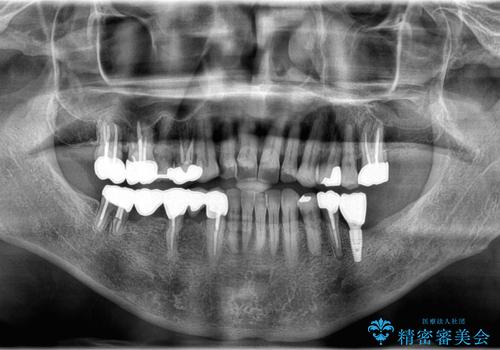

【インプラント】銀歯が取れて歯ごと折れた

- 「奥歯の銀歯が取れた」を主訴に来院された患者さんです。

診査診断を行った結果、歯が折れた位置が深く、虫歯にもなっていたため抜歯後、インプラントで治療を行いました。

残根状態の歯を抜歯後、抜歯窩の治癒を待ちインプラントを埋入しています。

アバットメントの材質は咬合力を考慮しチタン合金にしました。

被せ物はオールセラミッククラウンを入れています。